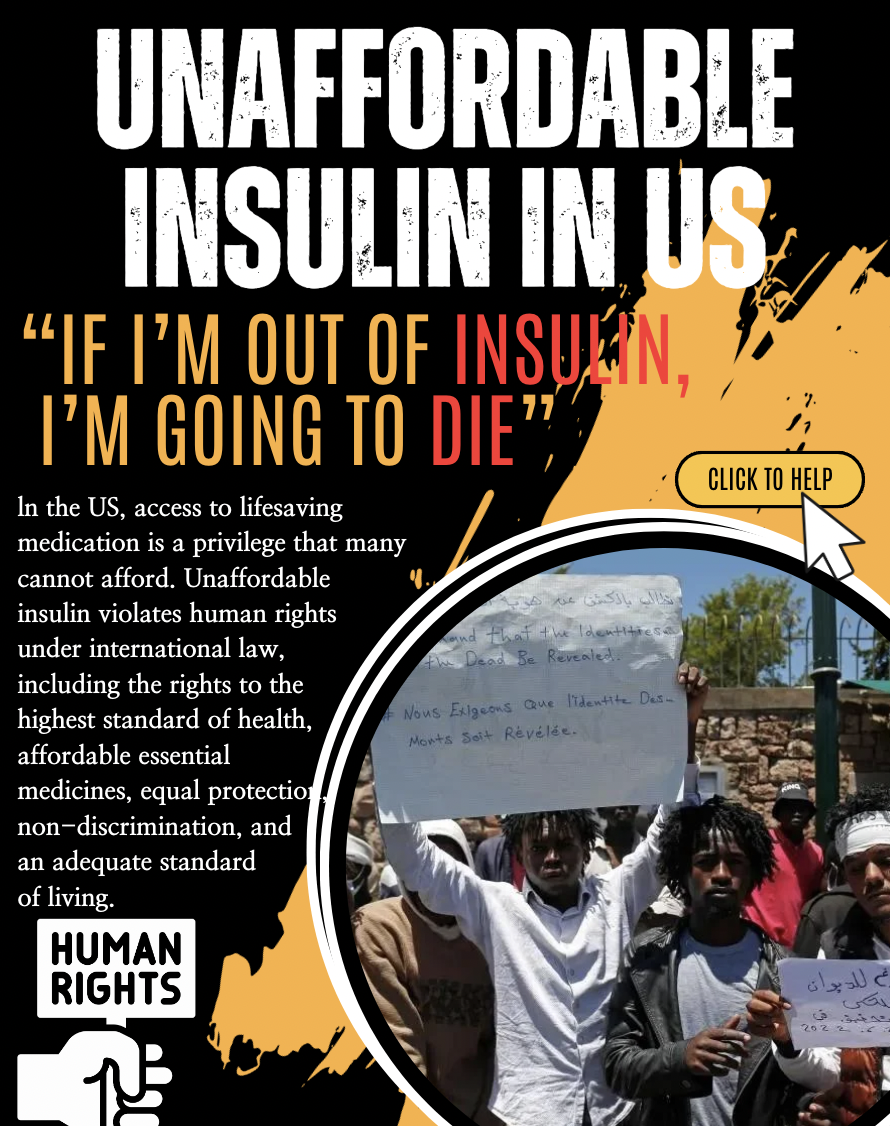

Founded a social justice club with the members of Spread:Dance to initiate awareness campaigns about global and human rights issues that are often overlooked.

Organized and led annual street campaigns in Apgujeong, using sticker boards and posters.

Focused on conflicts overshadowed by the Russo-Ukrainian War, with 12 members.

Led the campaign as the president to highlight the forgotten wars and human rights abuses during the Iran-Israel conflict (encouraged 16 members to engage with passersby using visual tools actively).

MY POSTERS